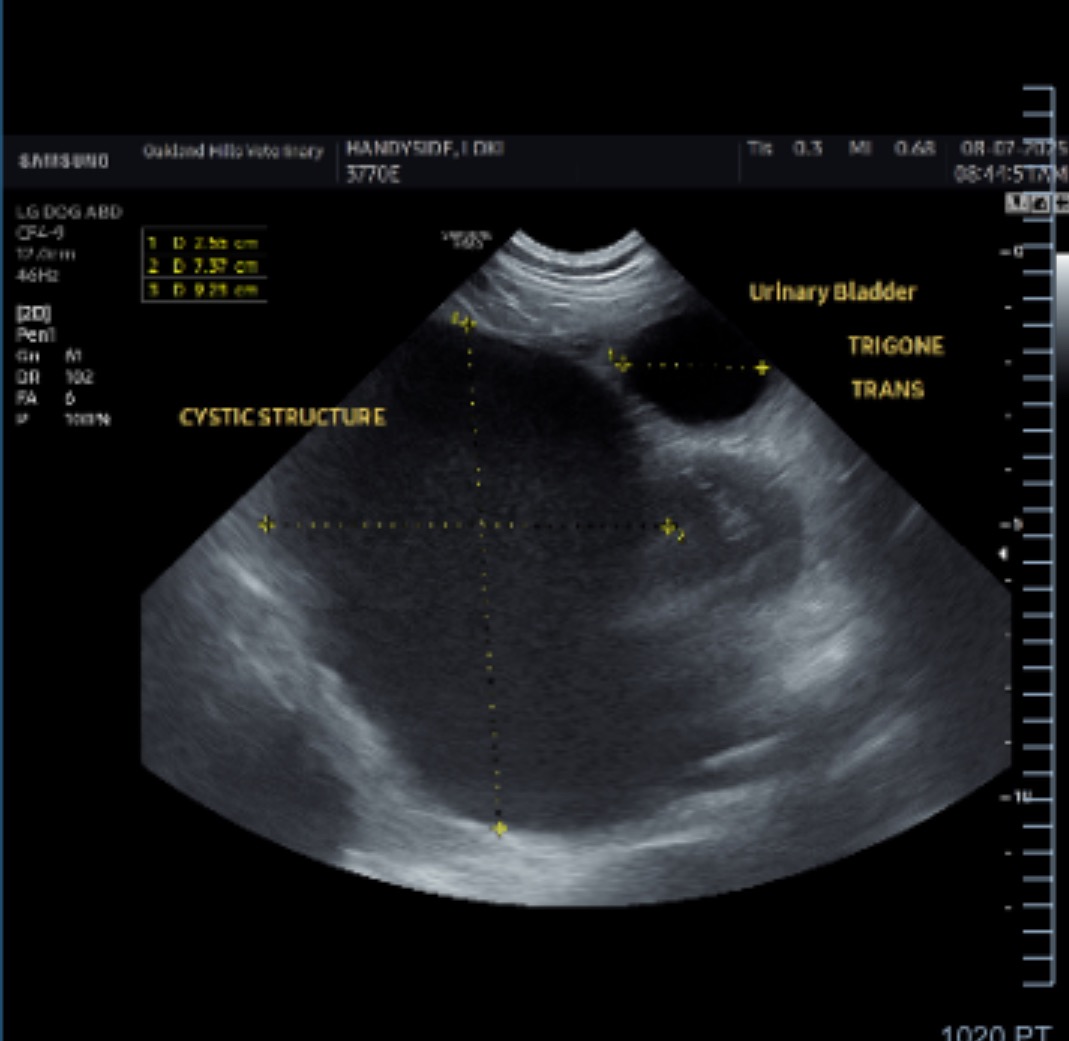

Hi, my name is Audrey. Recently, my dad’s dog Loki has been experiencing some urinary issues. After multiple diagnostics, we found in an ultrasound that Loki has an obstruction next to his bladder. This obstruction requires an abdominal exploratory surgery. The doctors aren’t sure exactly what this obstruction is, but it is a fluid filled mass causing disruption in Loki’s abdomen. This can get very serious very quickly if we don’t take care of it. On top of that, he’s being treated for a UTI due him not being able to urinate properly.